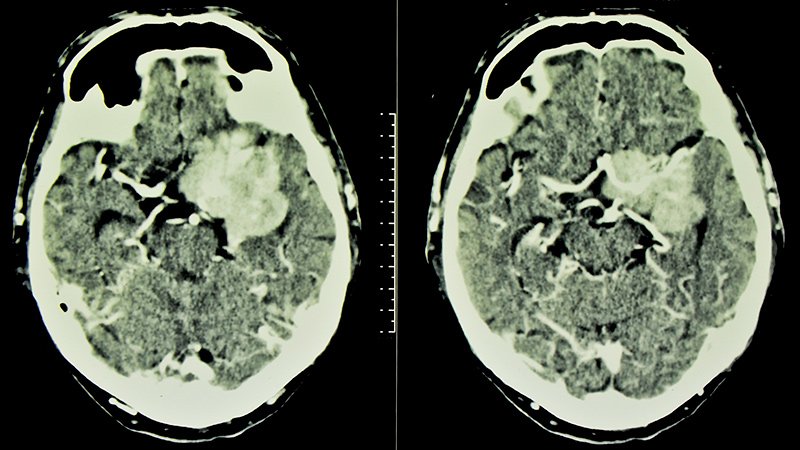

“A large proportion of meningiomas involve the skull base, which is of considerable importance because skull base meningioma surgery is one of the most challenging forms of surgery and is associated with a much higher risk than surgery for convexity meningiomas,” he told Medscape Medical News.

The current study revealed an association between prolonged use of cyproterone acetate with an increased incidence of meningiomas, and the sphenoid-orbital meningioma location was specific for the drug use. “It is unclear from the study if all the meningiomas were benign,” she said. “Even if they are benign, they can cause severe morbidity, including seizures.”